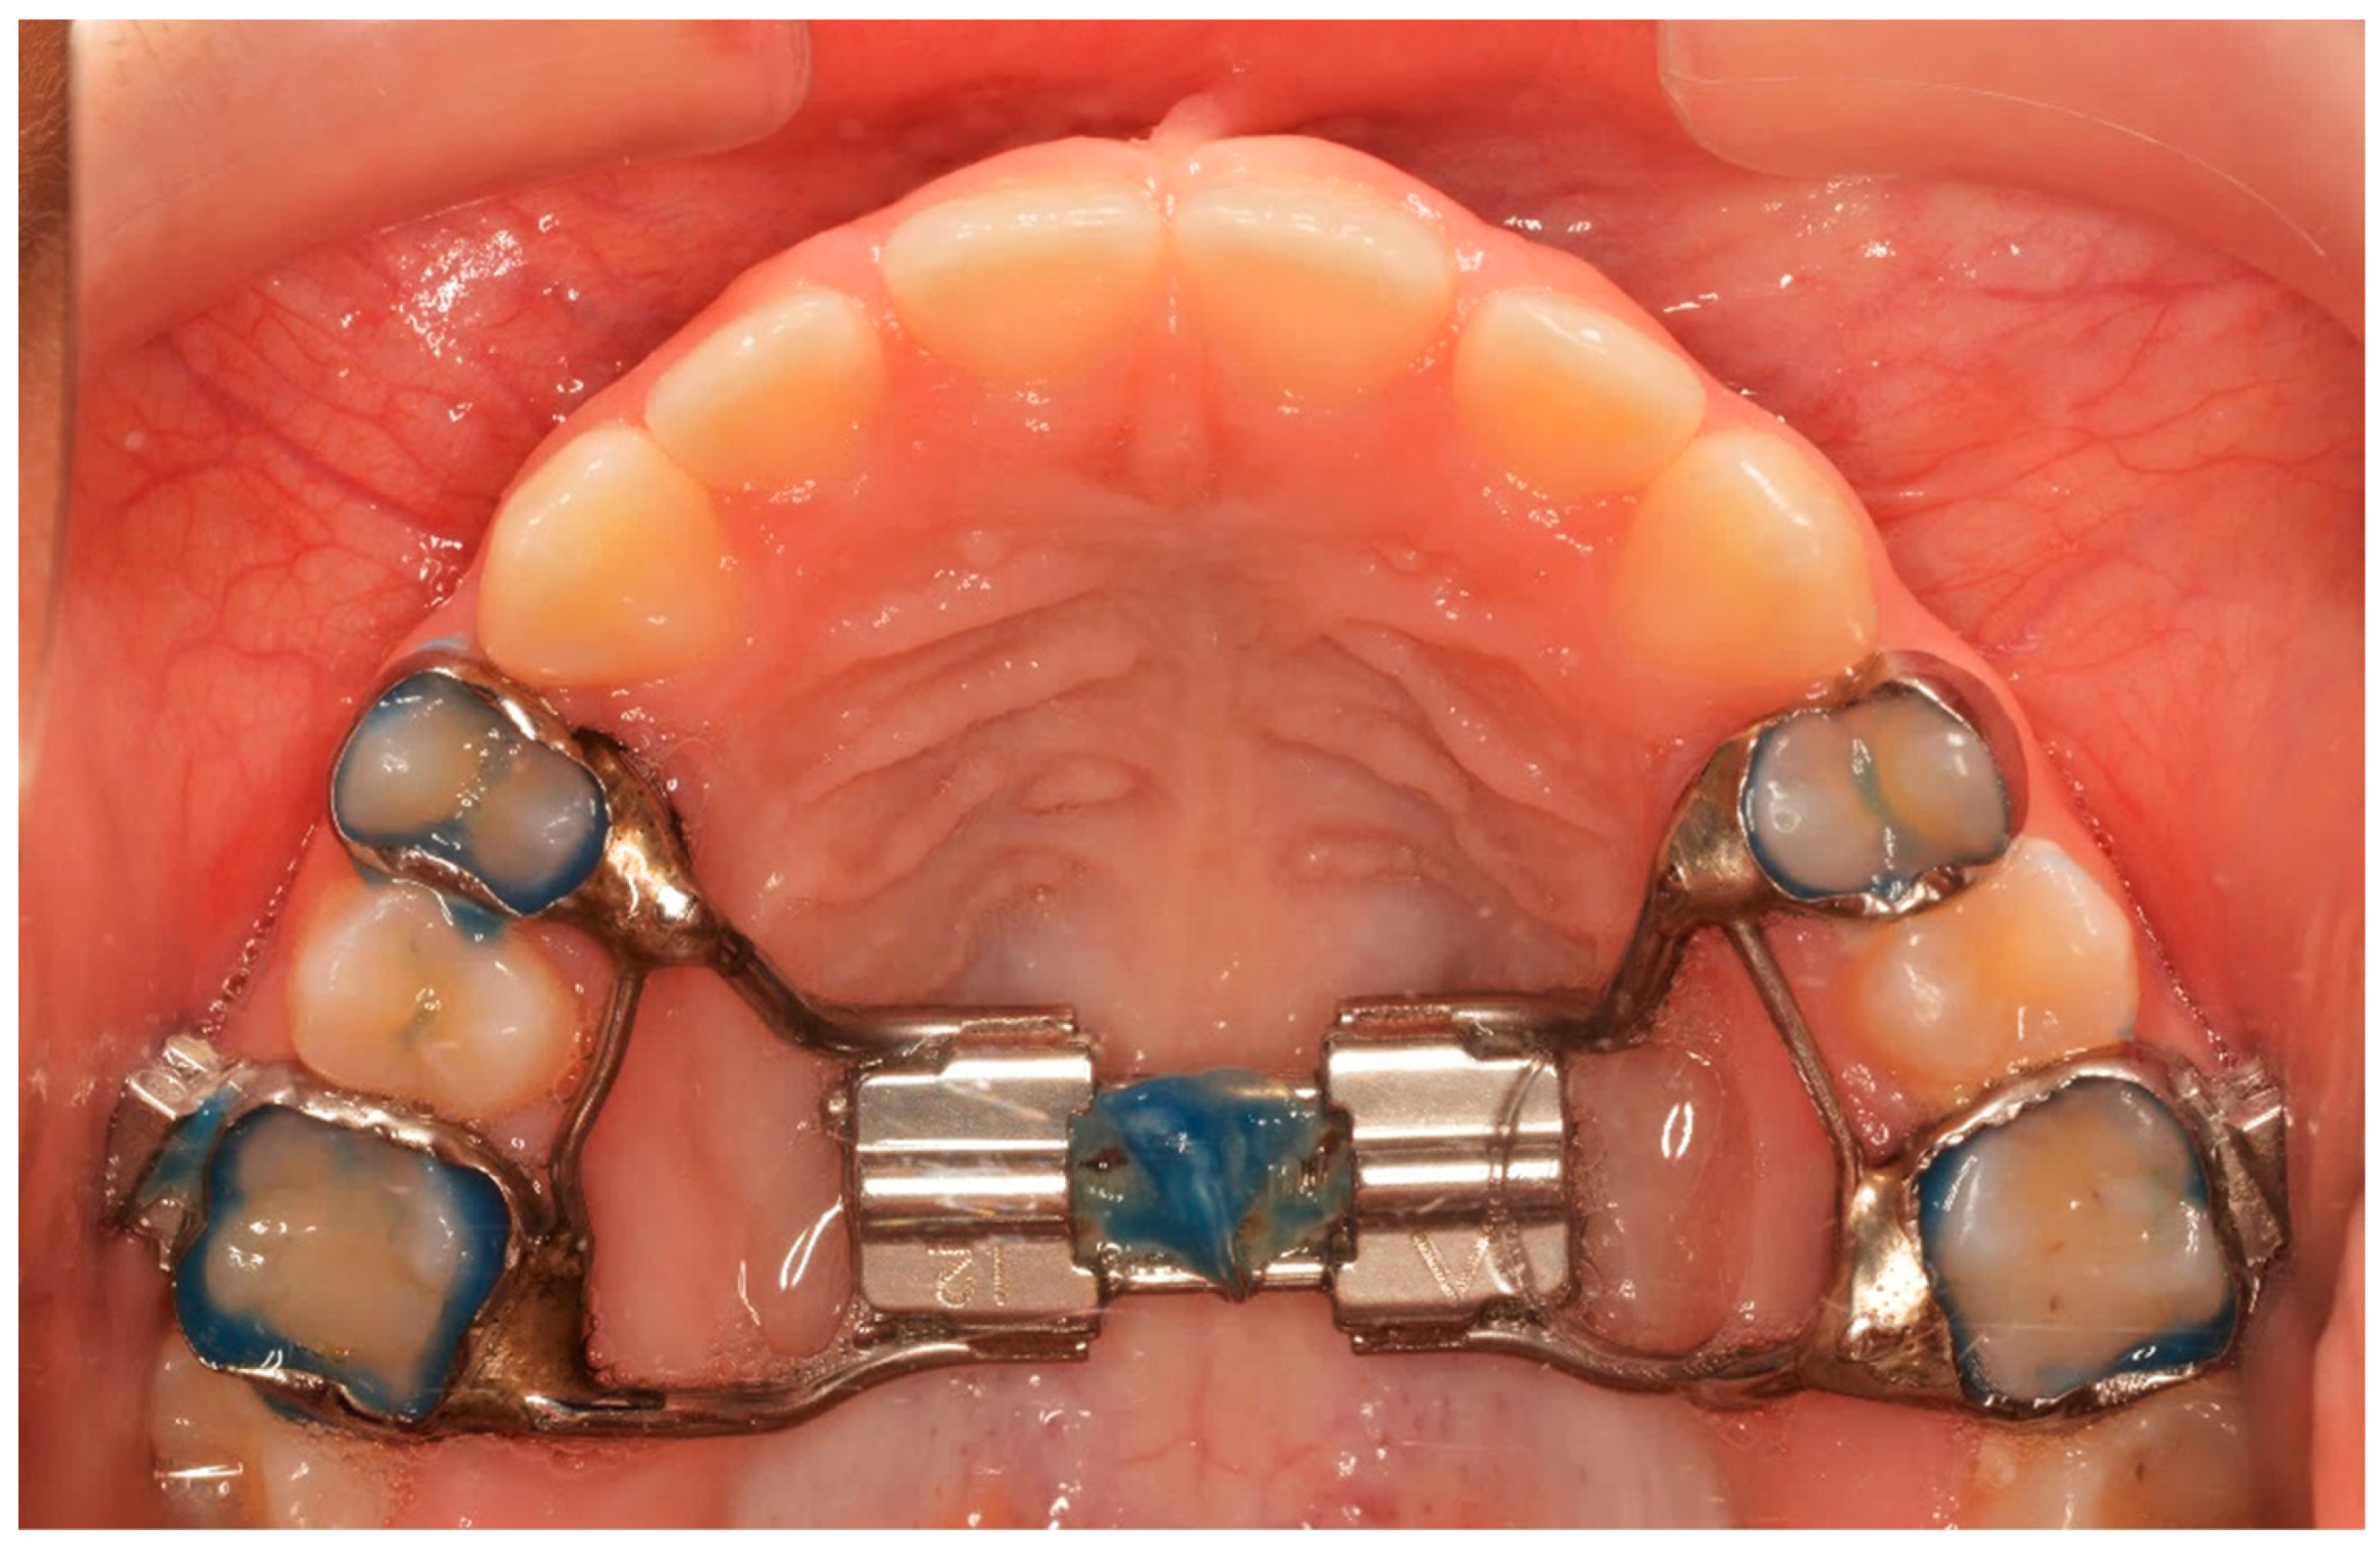

All patients received a Hyrax expander, as the initial part of their treatment, with bands cemented at least on the first maxillary permanent molars and on the first premolars or maxillary deciduous first molars. All Hyrax expanders were manufactured by the same laboratory, and all screws were by the same company. The expansion screw was activated twice a day (0.25 mm per turn, 0.5 mm daily) until the palatal cusp of the maxillary first molar occludes with the buccal cusp of the mandibular first molar. At the end of expansion, the Hyrax screw was stabilized with ligature wire and light-cured composite (Figure 1).

Figure 1.

The end of the active phase of expansion.